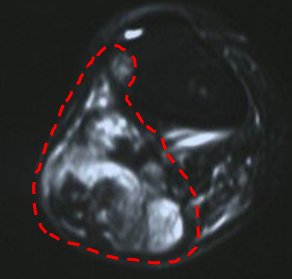

MRI, that is, magnetic resonance imaging, has a very important place in orthopedic oncology. MRI is particularly useful in demonstrating soft tissues. It is the most accepted method in bone tumors with soft tissue components and all kinds of soft tissue tumors. On the other hand, the shots must be done correctly. Otherwise, it is inevitable that the patient will have to undergo MRI several times. This means a waste of time. Especially in malignant bone tumors, MRI is of great importance so that the whole bone can be seen (pic-28). The patient should not be intervened until a sufficient quality MRI is taken. MRI must be taken with intravenous contrast material.